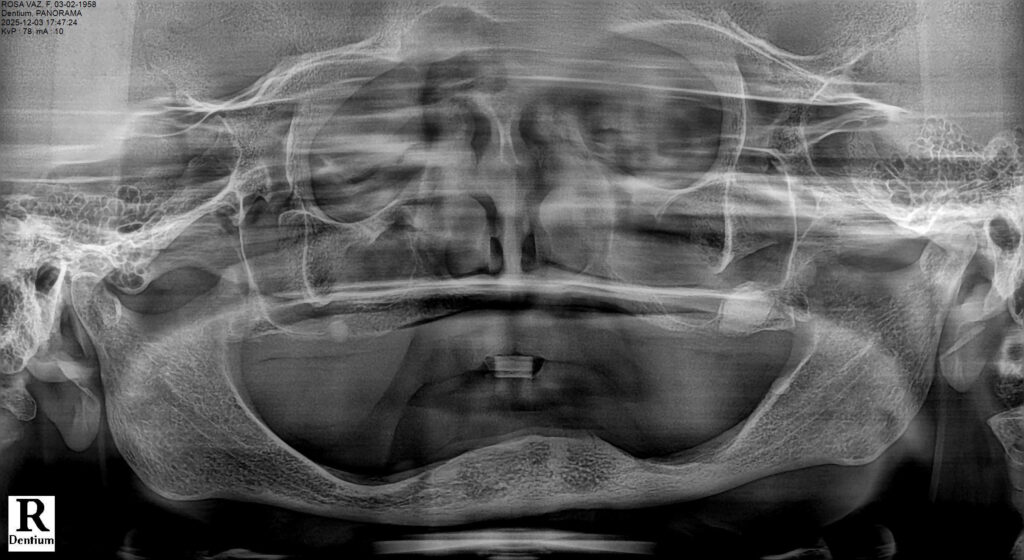

The patient presented with complete edentulism of the maxilla associated with Kelly syndrome, characterized by advanced anterior ridge resorption and flabby tissue.

Radiographic evaluation revealed severe pneumatization of the maxillary sinuses and limited residual bone height and width. In the mandible, the inferior alveolar nerve was located in the region of the first premolars, restricting posterior implant placement.

A comprehensive diagnostic work-up was performed, including panoramic radiography and cone-beam computed tomography (CBCT), to assess bone volume, sinus pneumatization, ridge morphology, and the position of critical anatomical structures.

The maxillary arch presented severe horizontal and vertical bone resorption, advanced sinus pneumatization, and a palatal shift of the residual ridge, consistent with Kelly syndrome. In the mandible, CBCT analysis revealed an anteriorly positioned inferior alveolar nerve in the premolar regions, limiting the safe placement of implants in these areas.